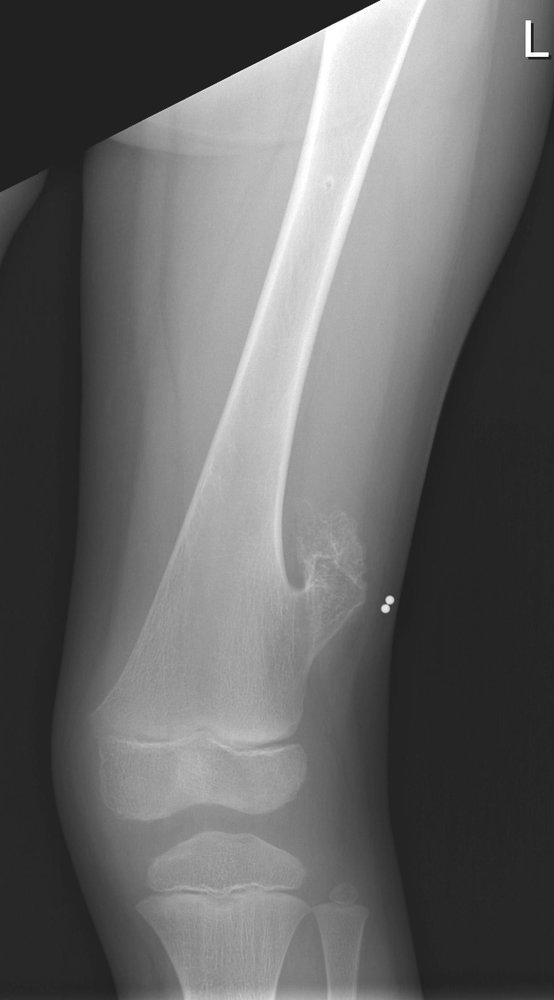

• Description: benign but locally aggressive tumor composed of giant cells that arise from the bone marrow [1]

• Epidemiology: peak incidence between 20 and 40 years

• Clinical features

• Found in the epiphysis or metaphysis of long bones (especially knee region)

• Pathological fractures

• Local pain and swelling

• Limited range of motion

• Diagnostics

• X-ray: multicystic osteolytic lesions (soap-bubble appearance)

• Histopathology

• Mononuclear, RANKL-expressing cells (neoplastic)

• Multinucleated giant cells (are reactive and resemble osteoclasts)

• Treatment: curettage and bone grafting or en-bloc resection to minimize recurrence rate

• Prognosis: risk of malignant degeneration increases with age; may spread to the lungs